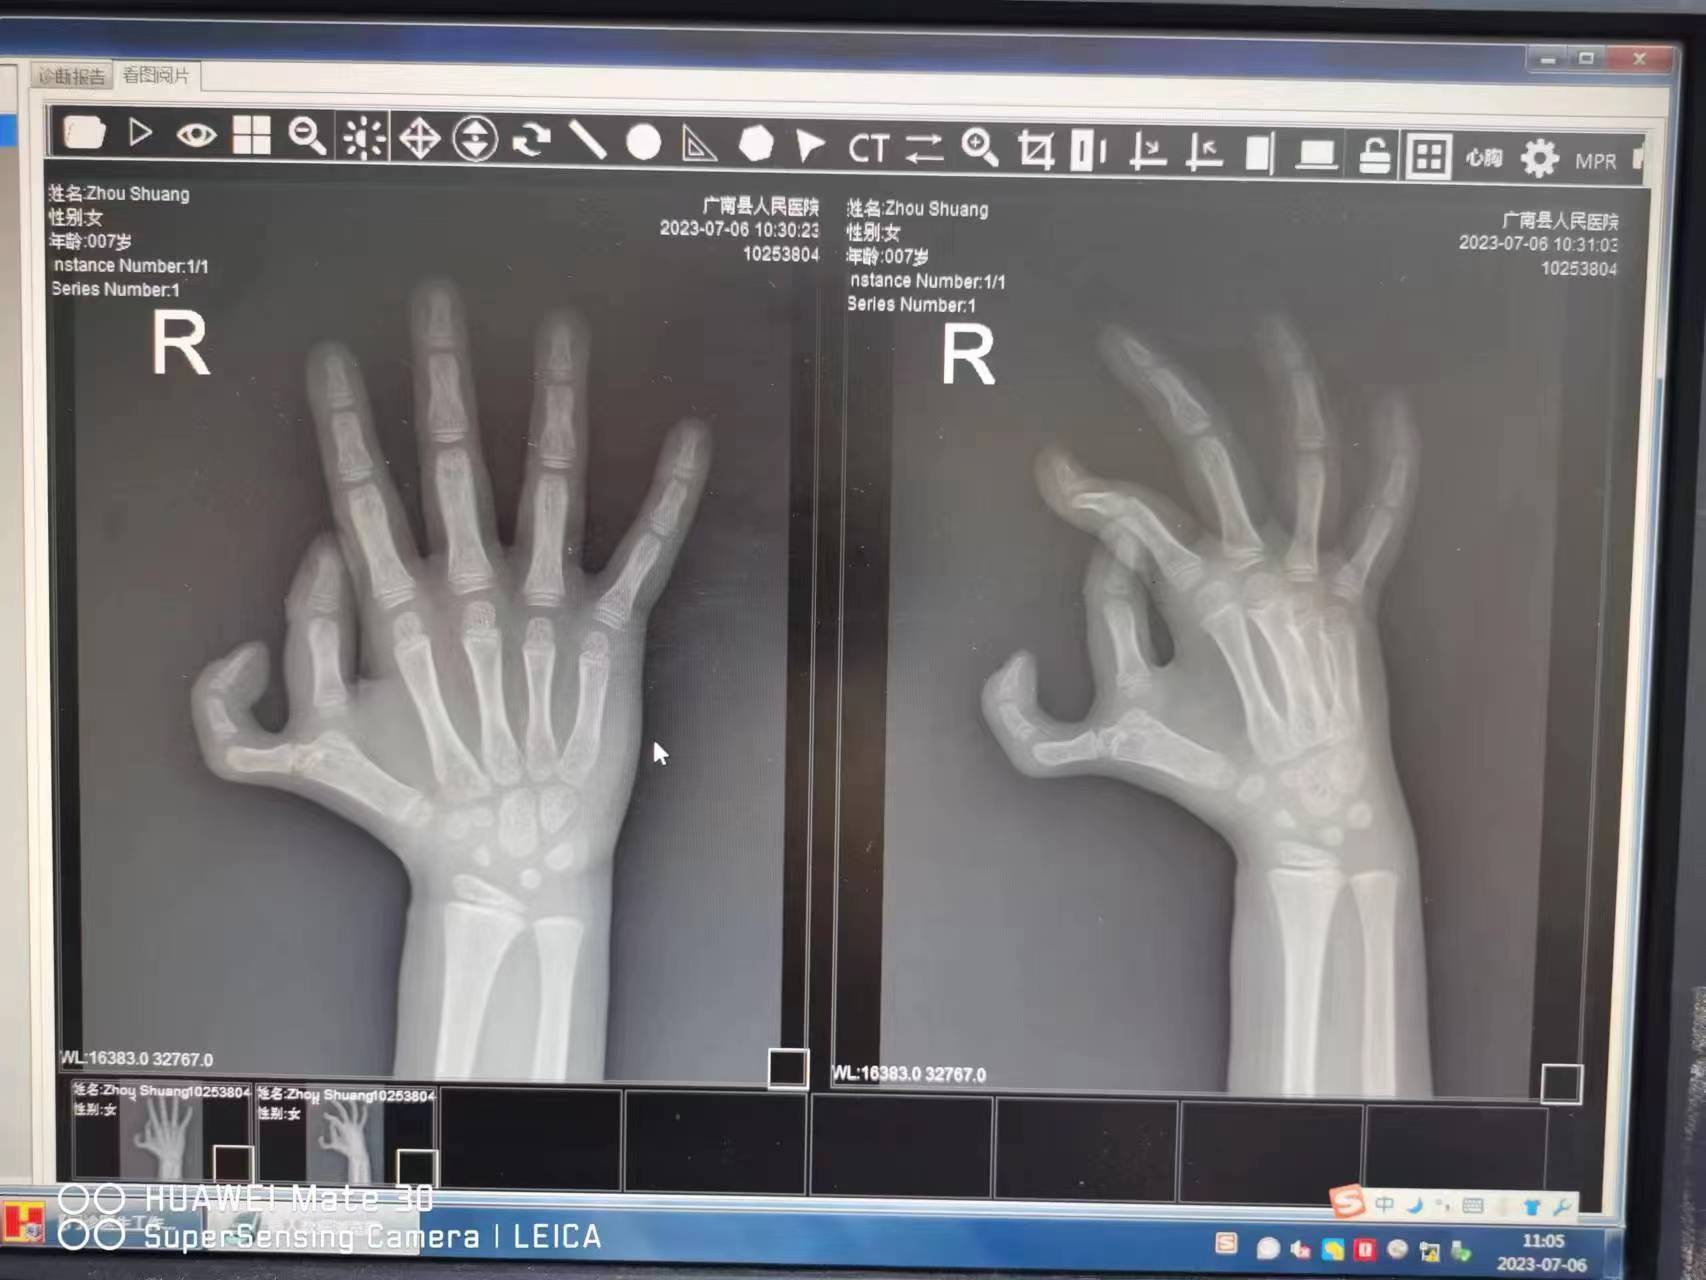

过去广南县人民医院收治的小儿骨科病人基本以骨折为主,矫形手术少有开展,而本次三例手术也开创了广南县儿童四肢畸形矫形手术的先河,尤其一位7岁女童,患有Wassel IVB型多指畸形,由于孩子治疗年龄偏大,合并软组织畸形和骨性畸形,相对正常的拇指功能缺失,需在保留相对正常拇指的血供的前提下通过一次手术解决外观和功能问题。这对手术医生来说操作难度较大,董良超在认真查体并在骨科主任张自明教授指导下制定了一个周全的手术方案,花费1个半小时,采用了涉及手外科近一半的术式给孩子做出了一个正常外观和功能的拇指。

图为董良超医生为广南县复杂多指患儿进行手术,根据术前的X线,制定手术方案,

术中完成多项复杂手术步骤,术后最终让患儿多指矫正后外观满意